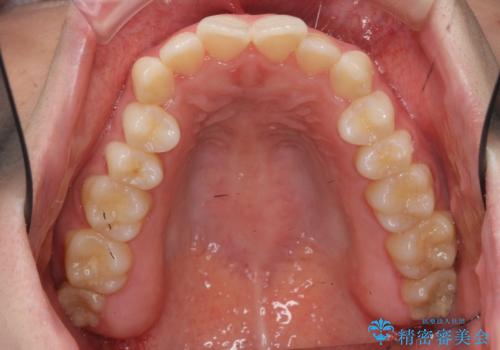

下の歯のがたつき 上より気になる

- 前歯のがたつきが気になって来院。

下の歯のがたつきが上よりも多い状態でした。

下の前歯は上の歯の内側にあるため、外に並べることができないため、上ほど簡単ではありません。

すき間をしっかりとって並べる必要があります。

今回は、下の歯を健康に支障が出ない範囲でわずかに削合し、並べるようにしました。(ディスキングといいます)

前歯のがたつきもしっかり治り、喜んでいただけました。